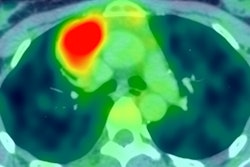

PET/CT images show a Hodgkin's lymphoma patient with a negative PET scan after chemotherapy. There is high uptake in lymph nodes on both sides of the neck prior to treatment (above), which resolved after chemotherapy (below). Physiological uptake is also seen in the heart and bladder. Images courtesy of Dr. Sally Barrington, reader in nuclear medicine, PET Imaging Centre at St Thomas' Hospital in London.